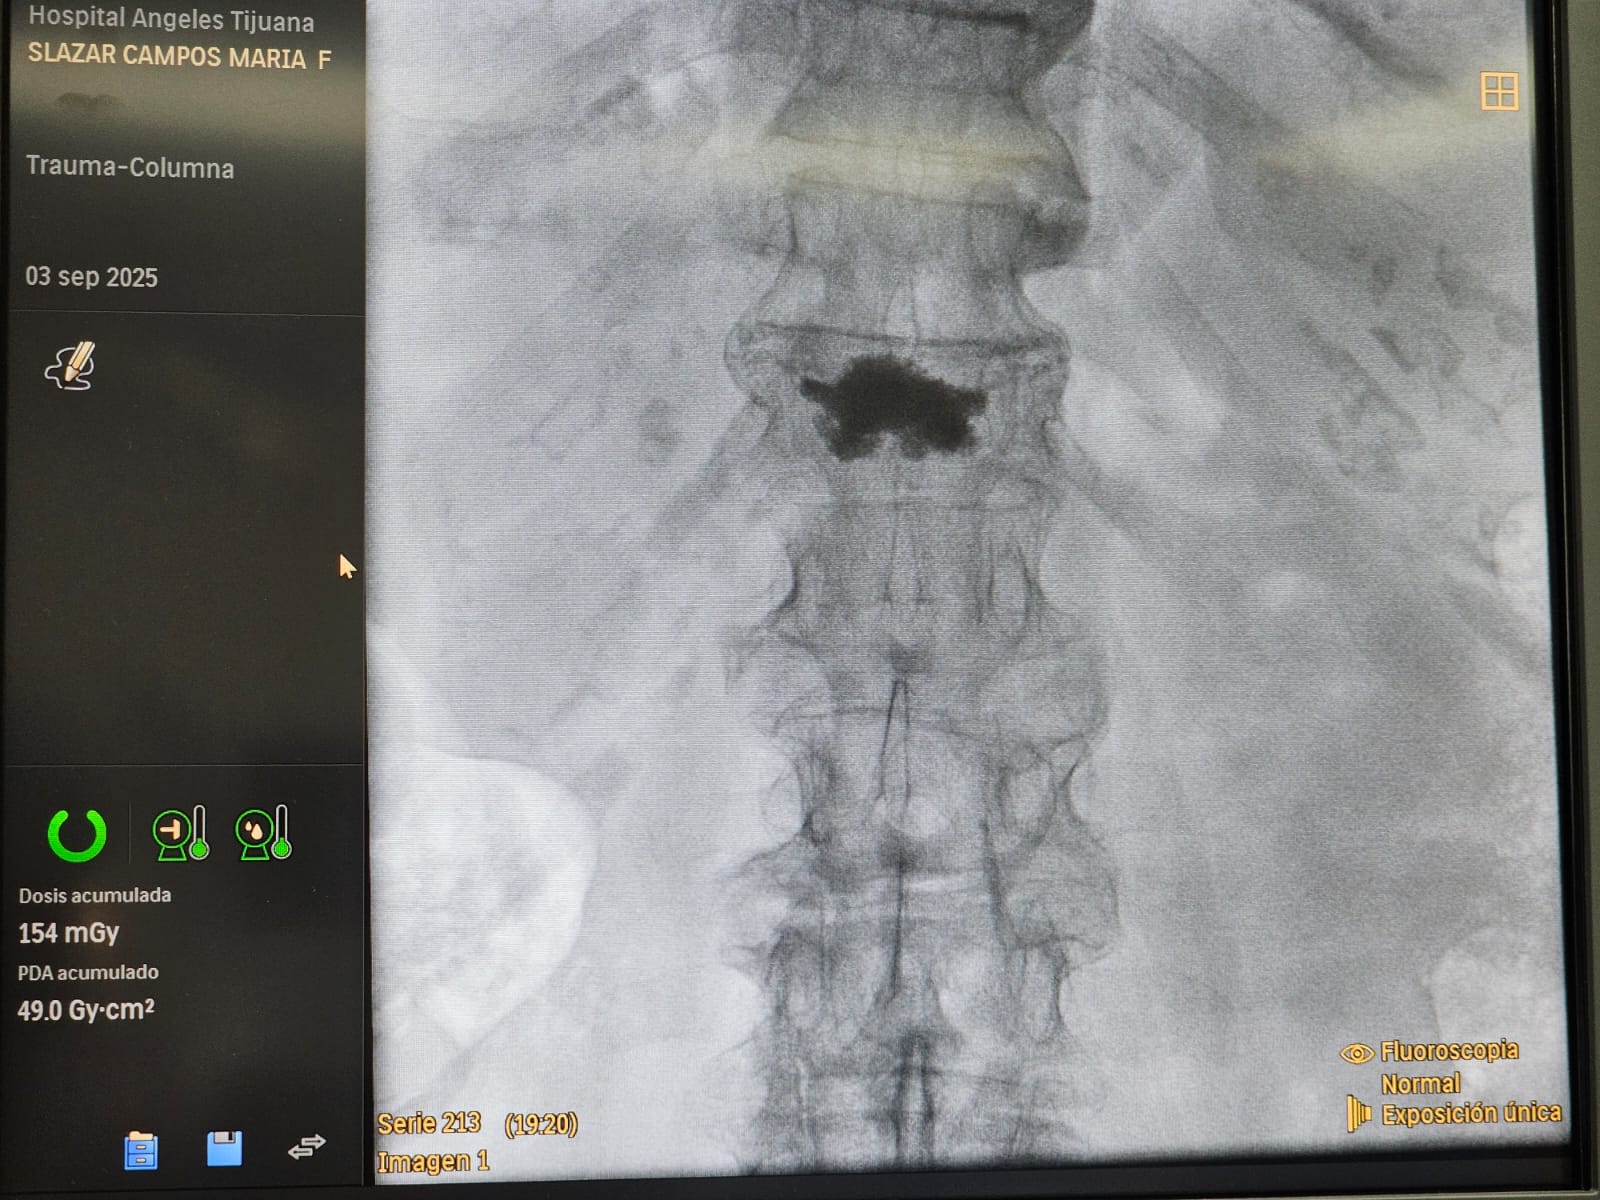

Cifoplastia

Reparación De Fracturas Vertebrales

• Procedimiento neuroquirúrgico enfocado en estabilizar y reparar fracturas en las vértebras de la columna, causadas por traumatismos, osteoporosis u otras condiciones.

A través de técnicas avanzadas y mínimamente invasivas, se busca restaurar la integridad estructural de la columna, aliviar el dolor y prevenir complicaciones neurológicas, garantizando una recuperación segura y funcional para el paciente.